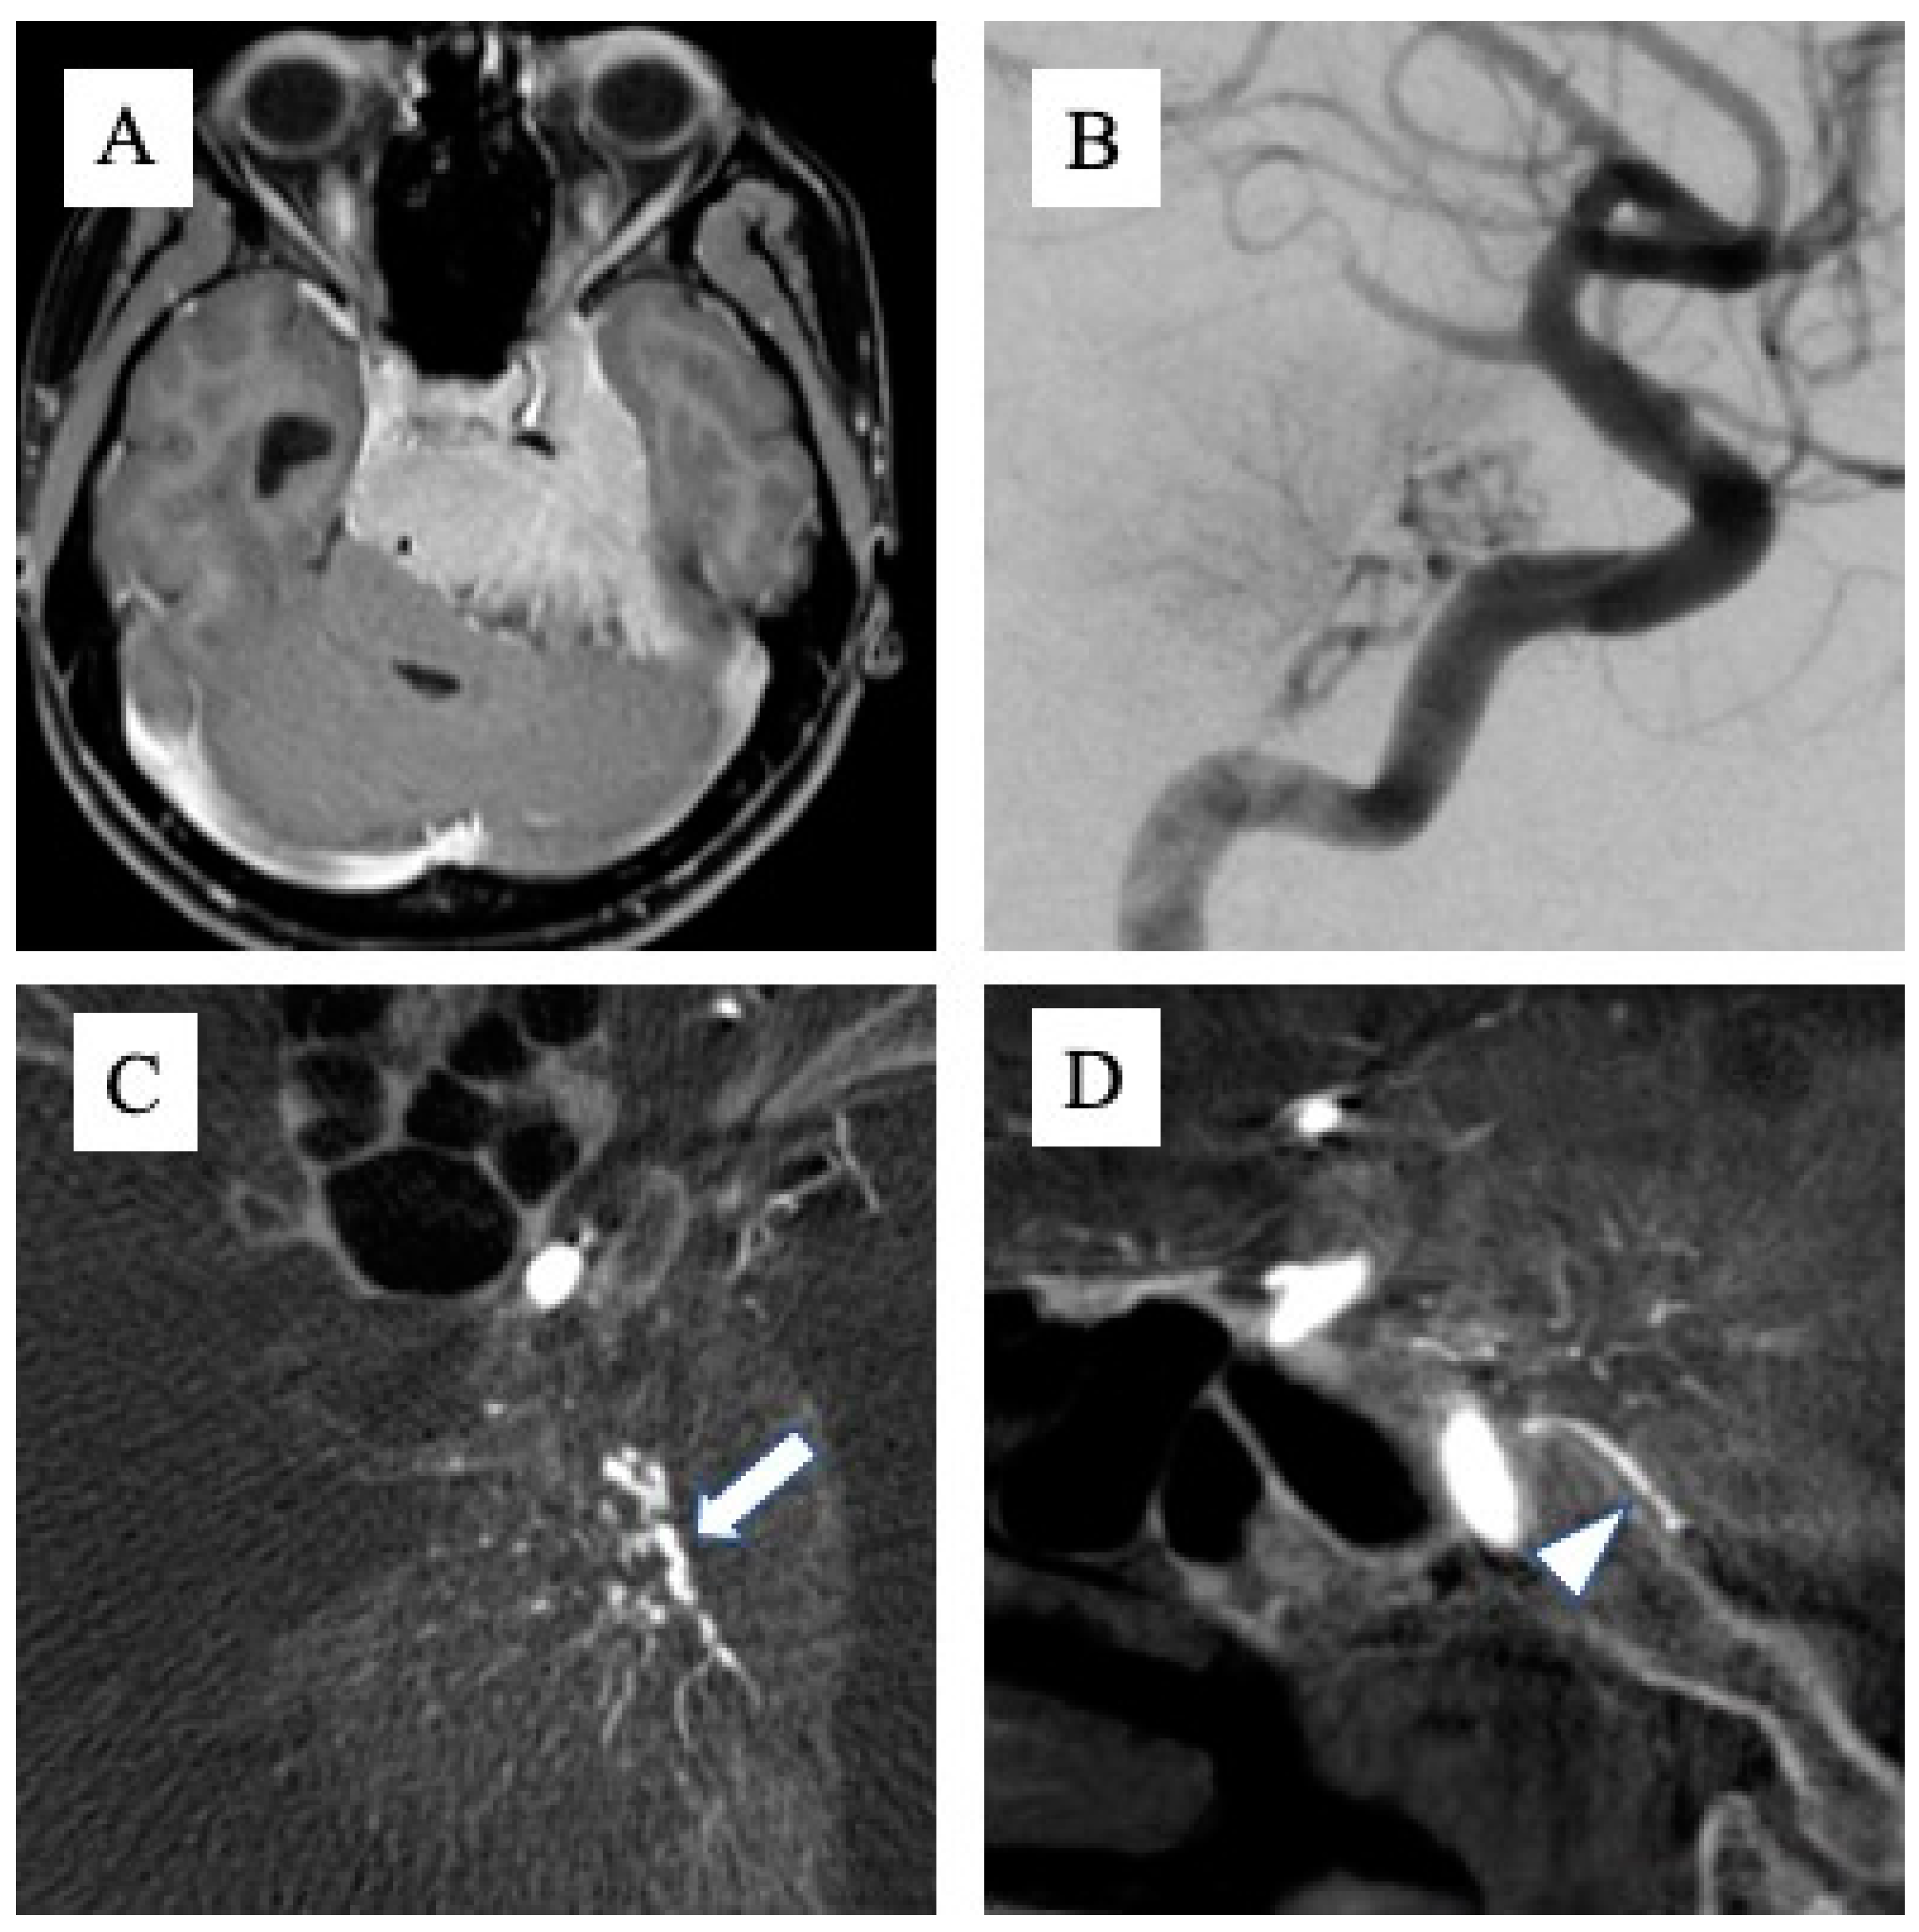

Tumor attachments were defined with reference to MRI T1-enhanced images (MAGNETOM Avanto 1.5T or MAGNETOM Vida 3.0T; Siemens Healthcare GmbH, Forchheim, Germany), and the part with a clear mass more than 2 mm thick and with obvious MRI enhancement was defined as the tumor attachment. The presence or absence of attachment to Areas 1, 2 and 3 was determined for each tumor, and if a wide range of attachments was seen across multiple areas, these were counted as duplicates. The feeding artery was determined from cerebral angiography (angiography system: Artis zee biplane; Siemens Healthcare GmbH). Digital subtraction angiography was performed using a 5-Fr catheter, with 8 ml of contrast medium at a rate of 6 ml/s for the common carotid artery (CCA), 6 ml of contrast medium at a rate of 4 ml/s for the internal carotid artery (ICA), and 5 ml of contrast medium at a rate of 3 ml/s for the external carotid artery (ECA) and vertebral artery (VA). Angiography from the CCA, ICA, or ECA was performed ipsilateral to the tumor in all cases. When tumor attachment was around the foramen magnum, angiograms were obtained from bilateral VAs. Contralaterally, an angiogram from the CCA was obtained first. If tumor staining was evident, angiography was added from the ICA or ECA to clearly visualize the feeding artery. In addition, cone-beam computed tomography (CBCT) from the ipsilateral CCA was taken in all cases, with 56 ml of double-diluted contrast medium injected at 2 ml/sec. When determining the feeding artery by DSA alone proved difficult, we referred to anatomical information that could be confirmed by CBCT, such as the running course of the artery (Figure 1A–D). Two endovascular specialists checked DSA and CBCT and defined the feeding artery of the tumor.

Figure 1. Cone beam CT obtained from digital subtraction angiography. When the feeding artery was difficult to define by 2D angiography, cone beam CT was helpful to determine the running course and accurately identify the vessel. A) Example of Huge meningioma with broad attachment. B) When various feeding arteries were visualized, it is difficult to define the accurate name of artery from 2D angiogram alone. C, D) The anatomical relationships and running courses of the tentorial artery (C: arrow) and dorsal meningeal artery (D: arrowhead) were easy to understand from cone beam CT.